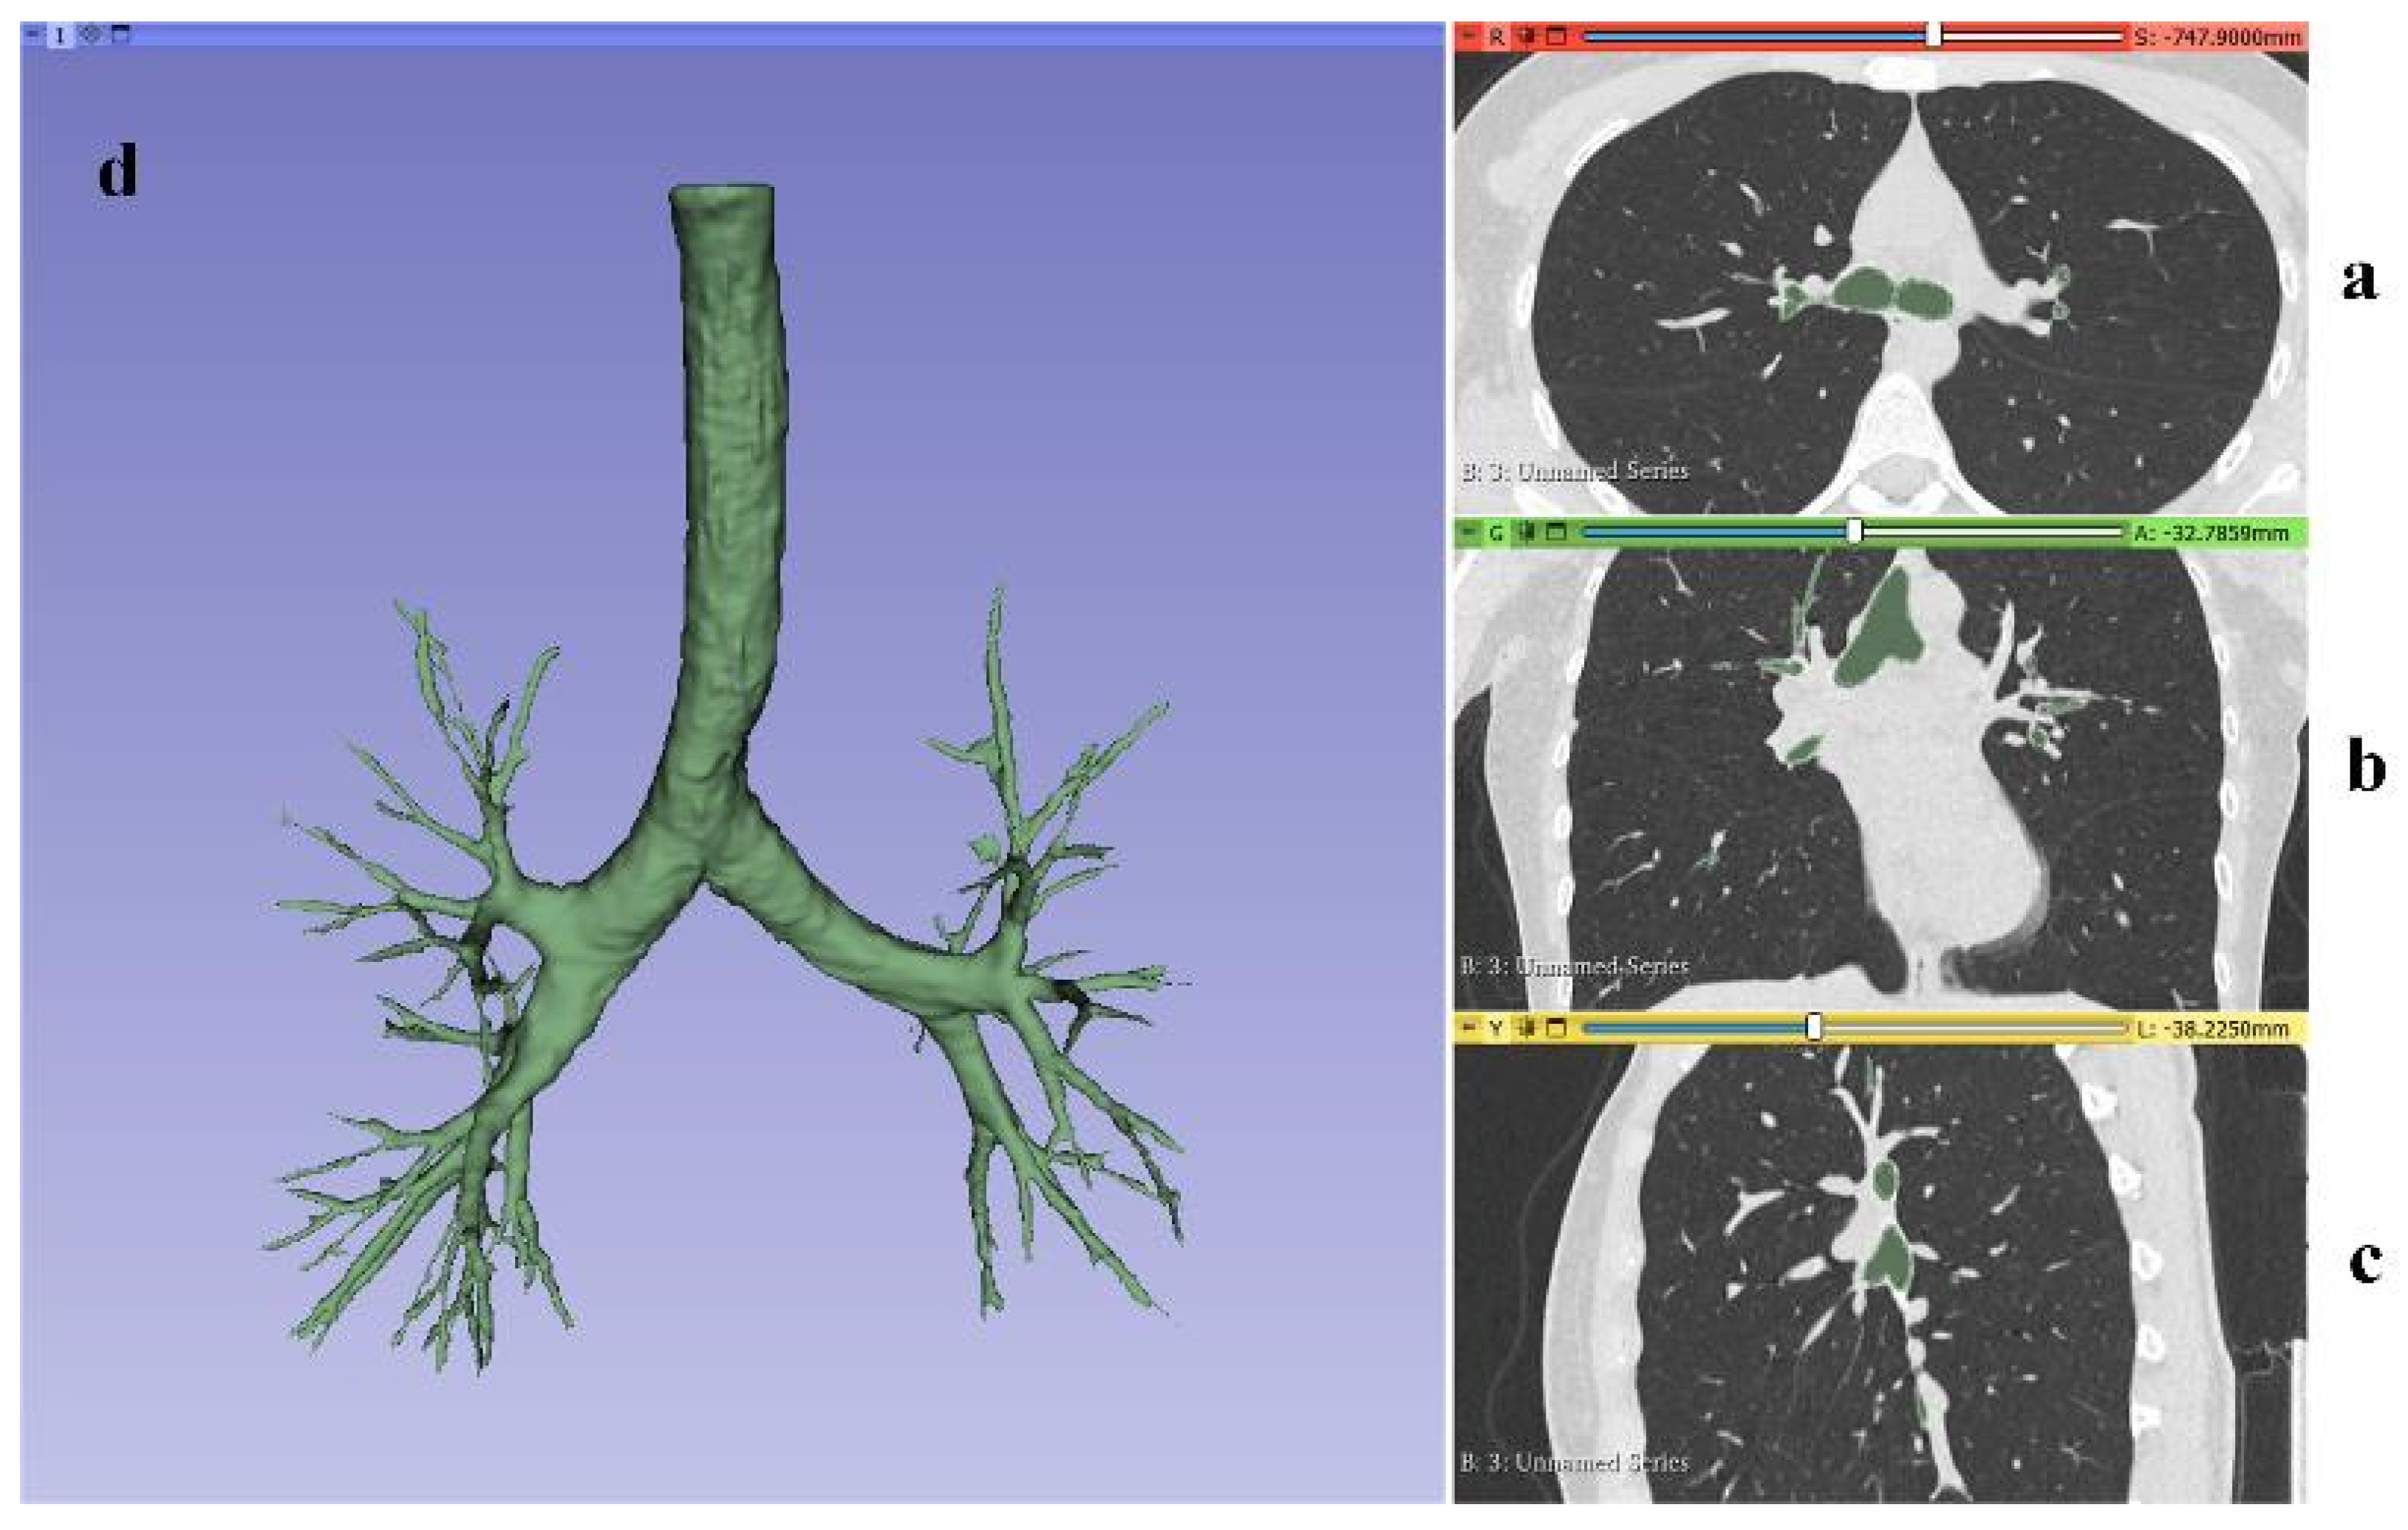

The automatic generation of the lungs’ 3D model from CT images resulted in the amalgamation of the bronchopulmonary trunk and pulmonary lobes into a singular 3D model, lacking the capability to differentiate between them. However, for the subsequent modeling of drug dispersion within the lower respiratory tract, isolating the bronchopulmonary trunk becomes imperative. Hence, CT images, loaded in three projections, underwent layer-by-layer processing using the Segment Editor toolkit in the 3D Slicer program. This meticulous process of identifying the free volume of the airways enabled the generation of a distinct 3D model representing the bronchopulmonary trunk. The outcome of processing the CT lung images and the resulting 3D model are depicted in Figure 7.

Figure 7. Layer−by−layer processing of CT images in three projections: frontal plane (a); sagittal plane (b); axial plane (c); generated 3D model of the bronchopulmonary trunk (d).